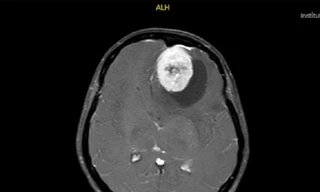

Hình ảnh chụp phim MSCT mạch não chảy máu não đồi thị - não thất do vỡ khối AVM (dị dạng thông động- tĩnh mạch não) bệnh nhân 15 tuổi. Ảnh: Bệnh viện Bạch Mai

Tình trạng khi vào Trung tâm Đột quỵ, Bệnh viện Bạch Mai: Ý thức hôn mê sâu, Glasgow 5 điểm, thở máy, giãn đồng tử bên phải. Kết quả chụp lại phim MSCT mạch não chảy máu não đồi thị - não thất do vỡ khối AVM (dị dạng thông động- tĩnh mạch não) biến chứng giãn não thất cấp, rối loạn thân nhiệt, sốt cao liên tục 39 - 40 độ C. Khối dị dạng mạch não tuy không quá lớn nhưng ở vị trí cực kỳ nguy hiểm. Mặc dù đã được hồi sức tích cực tại Trung tâm Đột Quỵ nhưng tình trạng diễn biến nhanh, bệnh nhân tụt huyết áp, thiểu niệu, rối loạn thân nhiệt, hôn mê sâu Glasgow 3 điểm. Sau 2 ngày điều trị, khi được bác sĩ giải thích không còn khả năng cứu chữa, gia đình đưa bệnh nhi về và bệnh nhi đã tử vong sau đó.